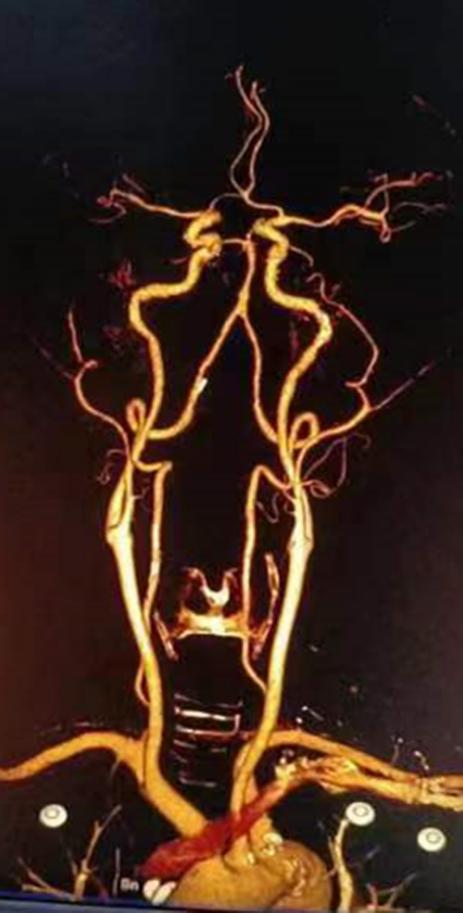

8月28日,商洛市管控区一名66岁男性突发右侧肢体无力,当地评估可能需要介入治疗,遂急诊转入我院。神经内科急诊介入团队第一时间响应,协助发热单元和影像科进行大血管CTA评估。鉴于患者大血管通畅,无急诊神经介入指征,遂制定了双联抗血小板治疗方案,并在感控部门评估后及时转入神经内科病房。目前患者肢体无力恢复正常,顺利出院。

图2 CTA显示大血管通畅